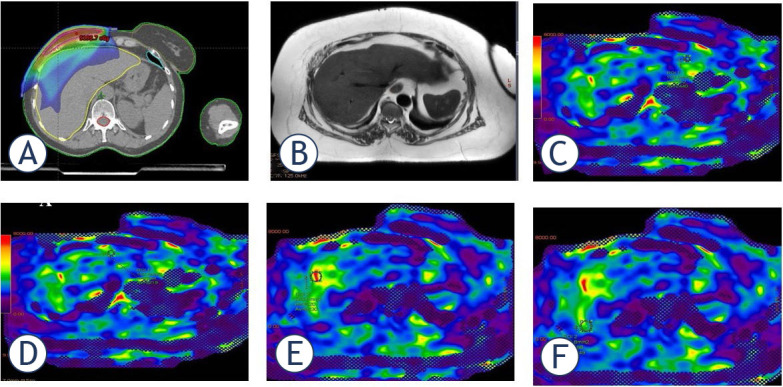

Background: In patients with right-sided breast cancer the liver can be partially irradiated during adjuvant radiotherapy (RT). We aimed to determine breast cancer RT effects on liver using with magnetic resonance elastography (MRE) and biological results.

Patients and methods: This retrospective study enrolled 34 patients diagnosed with right-sided breast cancer who underwent adjuvant RT. Liver segment assessments were conducted using MRE for all participants. Additionally, a complete blood count and liver enzyme analysis were performed for each patient. All measurements were taken both prior to the initiation and upon completion of RT.

Results: A statistically significant difference was found in ALT (p = 0.015), ALP (p = 0.026), total protein (p = 0.037), and albumin (p = 0.004) levels before and after RT. The highest mean liver stiffness (kPa) value was recorded in segment 8, while the lowest was observed in segment 6. A weak but statistically significant positive correlation was found between segment 5 stiffness and liver volume (p = 0.039). Additionally, a statistically significant positive correlation was detected between ALP levels and the stiffness values in segment 4A (p = 0.020) and segment 6 (p = 0.003). Conversely, a weak negative correlation was observed between the stiffness values in segment 8 and post-RT total protein levels (p = 0.031).

Conclusions: MRE can help us identify the level of fibrotic stiffness in the liver segments within the RT area without establishing clinical symptoms. MRE can support the clinician in evaluating the liver functions of right breast cancer patients who underwent RT. We assume these results will facilitate new studies with a large number of patients on MRE imaging at certain intervals in the follow-up of patients with right breast cancer who received RT before the development of radiation-induced liver disease (RILD).